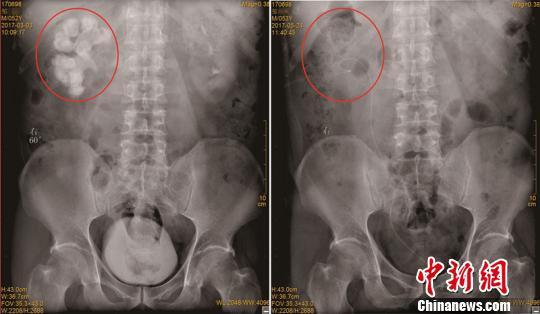

鄒先生手術(shù)前與第5次術(shù)后X光片對比圖。左側(cè)紅圈中白色輪廓為結(jié)石,右側(cè)為取凈結(jié)石后的右腎。陳松 攝

在四川結(jié)石病醫(yī)院,經(jīng)過仔細(xì)檢查,醫(yī)生發(fā)現(xiàn)鄒先生的結(jié)石已將其右腎空間填得嚴(yán)嚴(yán)實實,成為了一個“老姜”狀的鑄型結(jié)石,長端達(dá)到10厘米,同時右腎功能也僅剩2成左右。

面對鄒先生的巨大右腎結(jié)石,日前,竇醫(yī)平為其實施了多通道3鏡聯(lián)合分期手術(shù),歷經(jīng)5次手術(shù),包括4次經(jīng)皮腎鏡、輸尿管鏡碎石取石術(shù)、1次輸尿管軟鏡碎石取石術(shù),先后在其腰部建立了3個取石通道,才將鄒先生右腎內(nèi)的巨大結(jié)石粉碎并清除。手術(shù)中,醫(yī)生還為鄒先生處理了右側(cè)輸尿管狹窄的問題,進(jìn)一步減少了其結(jié)石再生的幾率。目前,鄒先生即將康復(fù)出院。